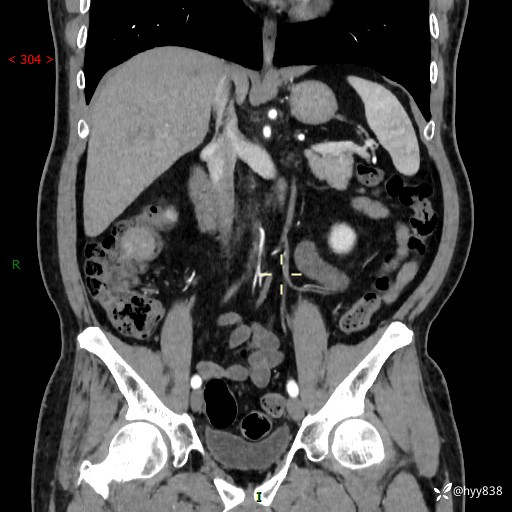

腹部CT增强扫描(外院CT平扫)

两期CT值:75hu 82hu